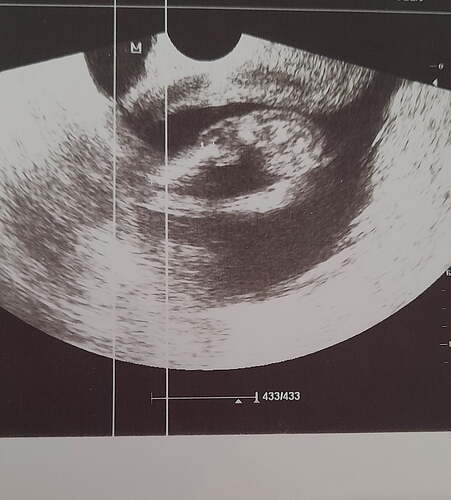

Ben kesenin fotosunu attım gözüküyor mu bilmiyorum sizce cinsiyeti bellimi

Kız kesesi gibi duruyor sağlıkla gelsin ![]()

@Hazalikko aşko kız gibi ama uzaktan kese fotosu var mı başka acaba